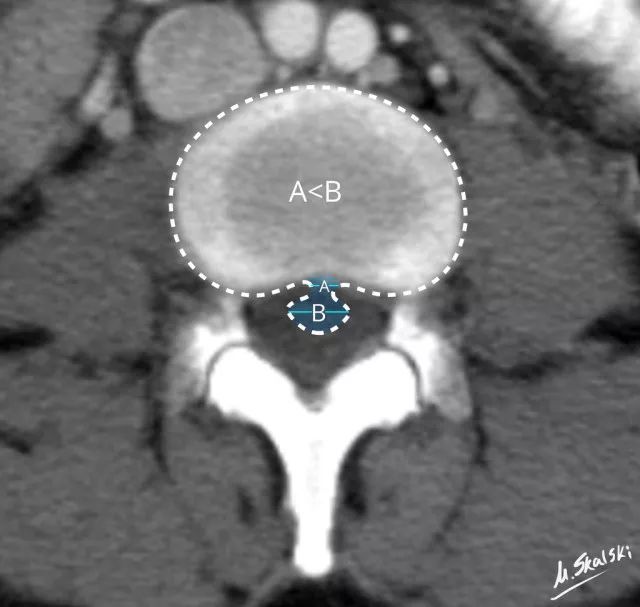

椎间盘脱出(Disc extrusion)

纤维环、后纵韧带完全破裂 , 髓核突入椎管内 。

椎间盘突出的影像学定义为突出椎间盘的基底部(A)<突出组织的直径(B)

临床表现

腰椎间盘突出的病理分型多有明显症状和体征 , 脱出多难自愈 , 保守治疗效果相对较差 , 大多需要微创介入或手术治疗 。